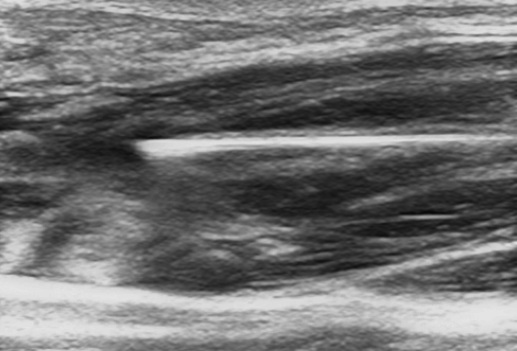

At CoreWave Vascular, we offer high-resolution vascular ultrasound imaging performed by an accredited specialist Sonographer holding a Diploma in Vascular Medical Ultrasound. Utilising advanced imaging technology and producing detailed, customised technical diagrams, we support accurate diagnosis and collaborative treatment planning to optimise patient outcomes.

Ultrasound Imaging Services

Vascular Investigation Studies